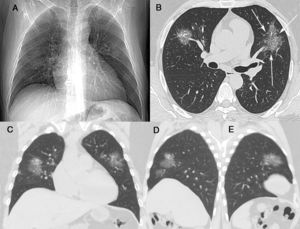

A 44-year-old man presented to the hospital (Centro Hospitalar do Porto, Porto, Portugal) on 7 March 2020 with a 6-day history of fever, cough, rhinorrhea, diffuse myalgia and fatigue. He had had close contact with a friend who had traveled to Milan, Italy, on 22–23 February 2020, during the COVID-19 pneumonia outbreak. On admission, the patient was in good general condition; he was tachypneic (respiratory rate of 30 breaths/min), his body temperature was 38.2°C, and cardiac auscultation was normal, with no murmur or arrhythmia. Pulmonary auscultation demonstrated the presence of sparse bilateral crackles. Laboratory tests showed a normal blood cell count, erythrocyte sedimentation rate of 84mm/h (normal=0–10mm/h), C-reactive protein level of14mg/L (normal=0.3–10mg/L), and unremarkable lactate dehydrogenase, creatine phosphokinase, and liver function findings. Blood gas analysis yielded normal findings (O2 saturation=98%). The patient's respiratory rate returned to normal after the normalization of his temperature. Non-enhanced chest computed tomography (CT) showed multiple round and oval ground-glass opacities in both lungs, with a crazy-paving pattern (Fig. 1B–D). No mediastinal lymphadenopathy or pleural effusion was present. Real-time reverse-transcription polymerase chain reaction of a nasopharyngeal sample revealed positivity for 2019-nCov nucleic acid. Hydroxychloroquine and symptomatic medication were administered. The patient recovered uneventfully and was discharged after 16 days in an asymptomatic state.

(A) A posteroanterior chest radiograph was considered normal. Unenhanced chest computed tomography with axial (B), coronal (C) and sagittal (D and E) maximum-intensity projection imaging demonstrated areas of ground glass opacity, many with round and oval morphologies, in both lungs. Not also in B inter- and intralobular septal thickening with a crazy-paving pattern (arrows).

Although our patient had pneumonia, as confirmed by CT, the chest radiograph was normal. Chest radiography has not been recommended as a first-line imaging modality for the diagnosis of COVID-19 due to its limited sensitivity in the detection of ground-glass opacities and other incipient pulmonary findings of the infection, which are evident on CT. However, nonspecific chest radiography findings have been reported occasionally, particularly for patients with severe disease.4,5 The role of CT in COVID-19 evaluation is the subject of much discussion. Some authors suggest that CT has a pivotal role, whereas other investigators are less optimistic. The predominant CT findings are multifocal, bilateral, peripheral, and basal-predominant ground-glass opacities, often with round and/or oval morphology and/or consolidation. The crazy-paving pattern may be observed. This pattern is defined as thickened interlobular septa and intralobular lines superimposed on a background of ground-glass opacities. Pleural effusion, small lung nodules, cavitation, and lymphadenopathy are very uncommon findings.2,5,6 These CT findings are not specific to COVID-19; similar results can be obtained for other infectious and non-infectious diseases.6

However, two characteristics of the ground-glass opacities may suggest the diagnosis of COVID-19 in the context of the current pandemic. The presence of multifocal nodular (round or oval) ground-glass opacities7,8 and/or the association of these opacities with reticulation (the crazy-paving pattern)8–10 should alert the radiologist to the possibility of COVID-19 infection. The latter finding appears particularly when the disease progresses. Our patient presented both findings. We believe that these two findings are important for the diagnosis of COVID-19, although the crazy-paving pattern is less specific; Amorim et al.11 observed it in 15% of 70 patients with confirmed H1N1 infection.